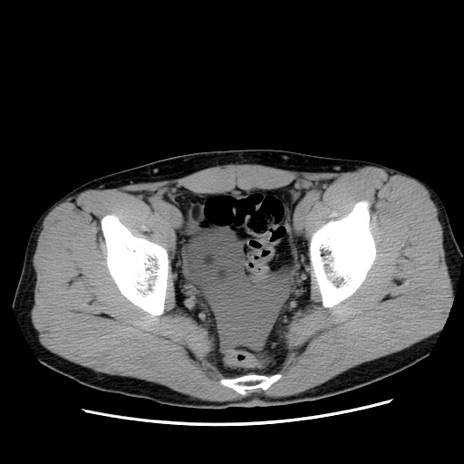

症例36(横断像)

【症例】20歳代 男性

【主訴】心窩部痛

【現病歴】今朝より上腹部痛あり。一旦軽快していたが再度出現したため救急要請。昨日夕に白身の魚を含む刺身を食べた。

【身体所見】BP 136/89mmHg、HR 74/min、BT 37.0℃、腹部:膨満、軟、心窩部に圧痛あり。反跳痛なし、筋性防御なし、腸雑音やや亢進あり。

【データ】WBC 17700、CRP 0.48